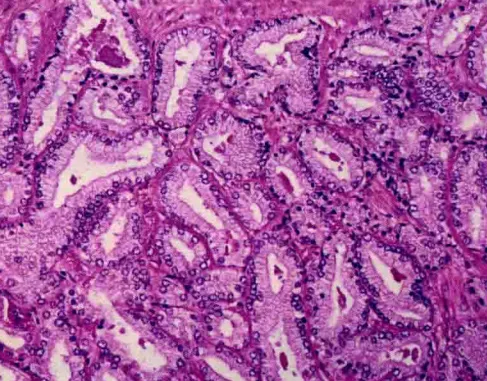

Gleason4级:包括融合性小腺泡群,呈不规则、互相吻合的筛状或乳头状结构;低分化腺癌由成簇细胞构成腺腔形成不良,腺体界限欠清;筛状结构腺体;肾上腺样结构,表现为胞质透亮、核小而深染的肿瘤细胞形成片状结构,似肾透明细胞癌。

Gleason4级,显示分化欠佳的腺体,可见簇状细胞及条索状结构,提示腺体形成,但大部分缺乏确切的腺腔

相互融合的腺体

筛状结构